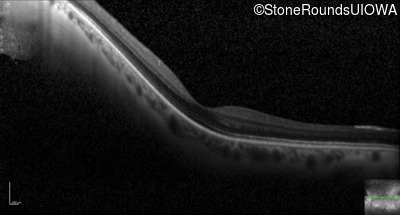

Optical Coherence Tomography - Left - 20/25 +2

Exemplar / OCT Stack